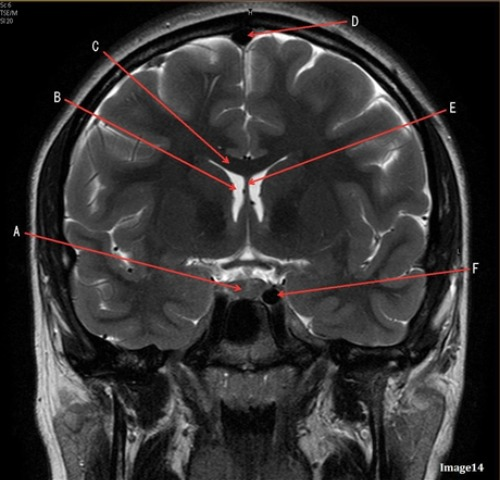

Letter A in image 14 is pointing to:

D. Pituitary gland

Letter F in image 14 is pointing to:

D. Internal carotid artery

Image 11 is an example of a _______ weighted sequence acquired in the _______ scan plane.

D. T2; Coronal

Letter E in Image 14 is pointing to:

E. Fornix

Letter D in Image 14 is pointing to:

D. Sagittal sinus

Letter B in Image 14 is pointing to:

C. Lateral ventricle

Letter C in Image 14 is pointing to:

A. Corpus callosum